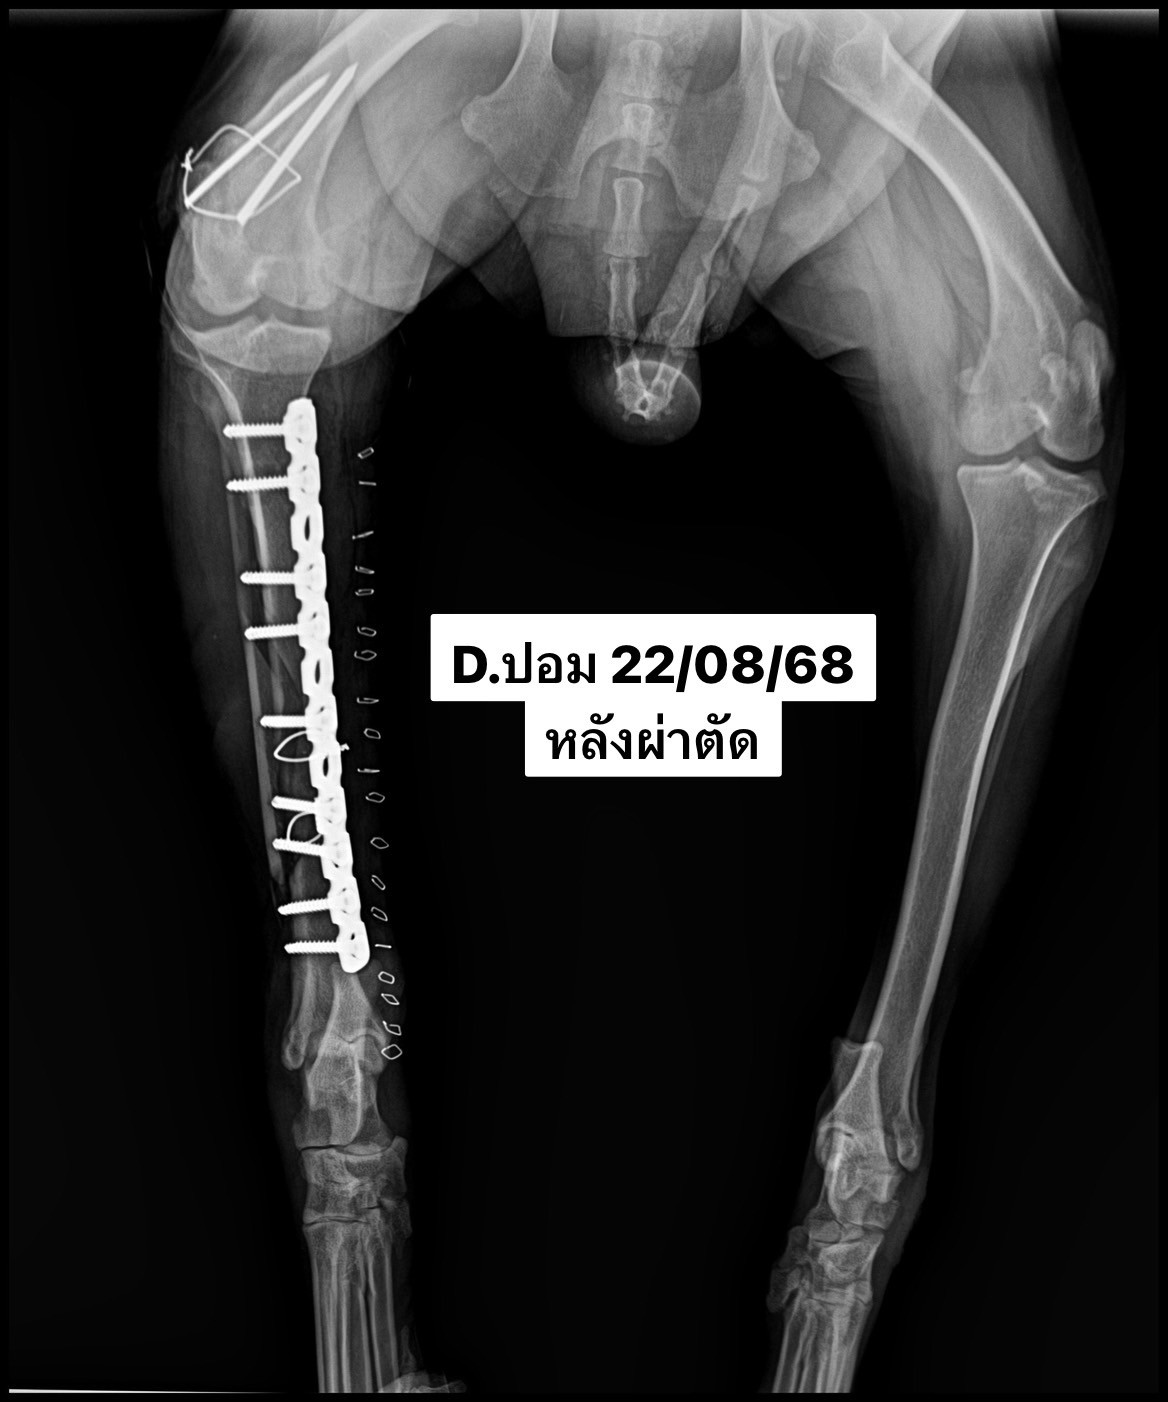

สัตวแพทย์จึงวางแผนการรักษาด้วยการ ผ่าตัดใส่แผ่นเหล็กตรึงกระดูกและมัดลวดพิเศษทางการสัตวแพทย์ (medial plate and cerclage wire) เพื่อให้กระดูกยึดติดแน่นในแนวที่ถูกต้อง ช่วยให้น้องปอมสามารถฟื้นตัวและกลับมาใช้ขาได้ตามปกติในอนาคต